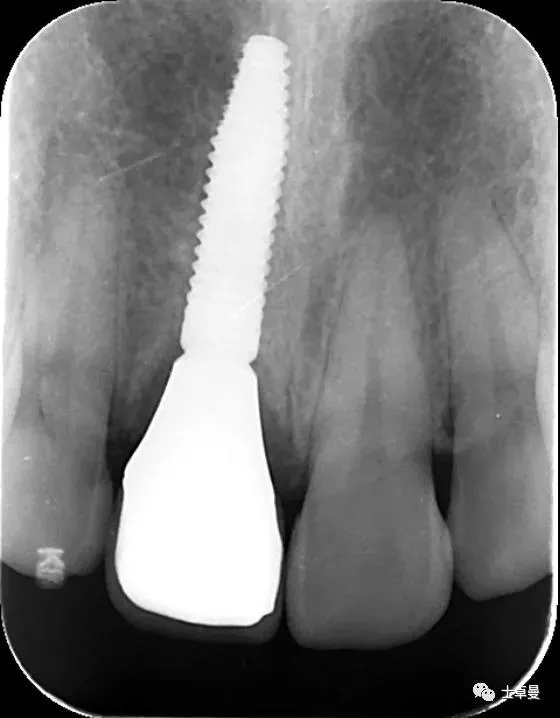

X线示,永久修复体已就位

术后4个月复查,种植体周未见明显暗影